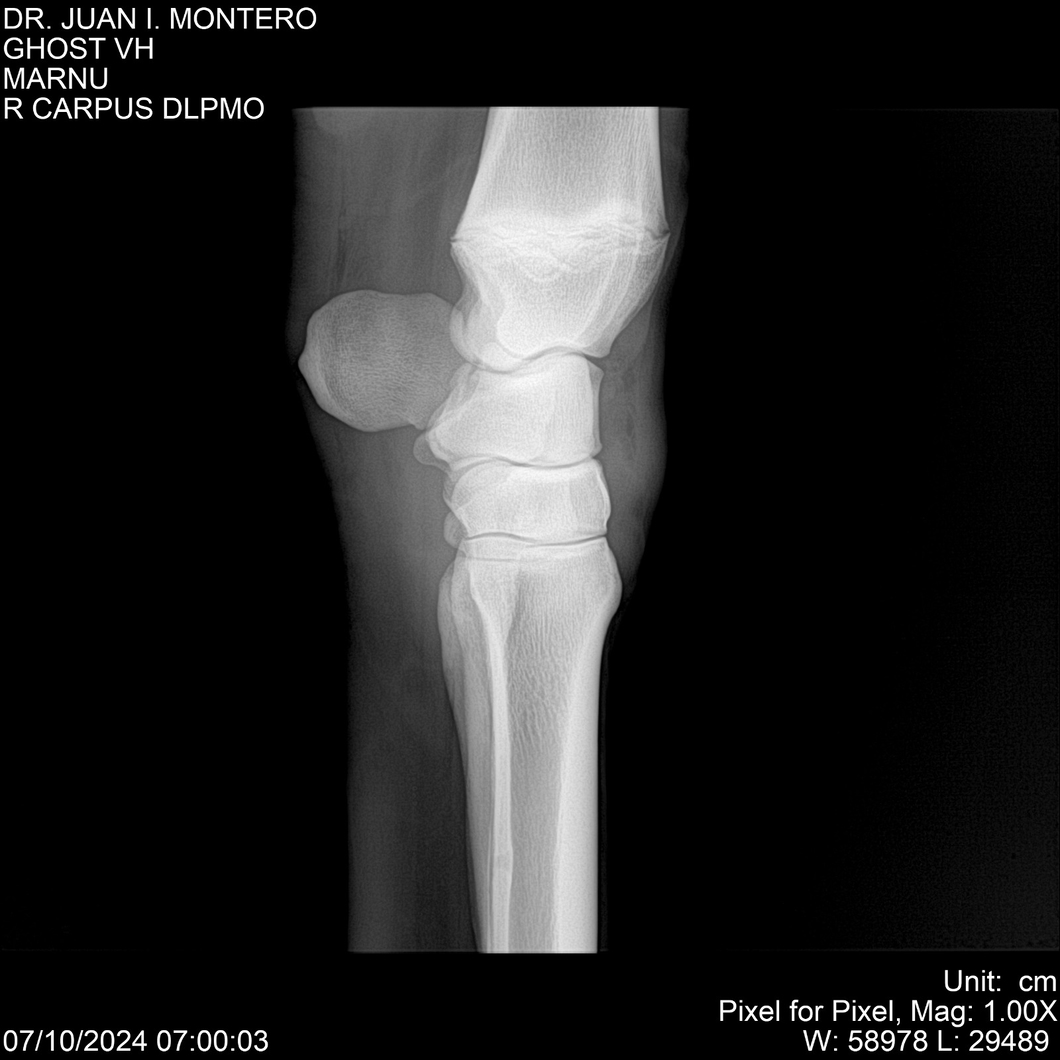

LOTE 15, GHOST VH 🔥 🔥 🔥 Lote Anterior Volver al remate Lote Siguiente Ficha Contacto Montevideo - Ficha del Lote Identificador: #282525 Categoría: Yeguarizos Montevideo - 69 Visualizaciones ClicData Contacto Empresa: Abelenda N. R., Walter Hugo Nombre*: Teléfono* : E-mail* : Mensaje Enviar Registrese gratis Este contenido Exclusivo está disponible sólo para usuarios registrados Ingresar